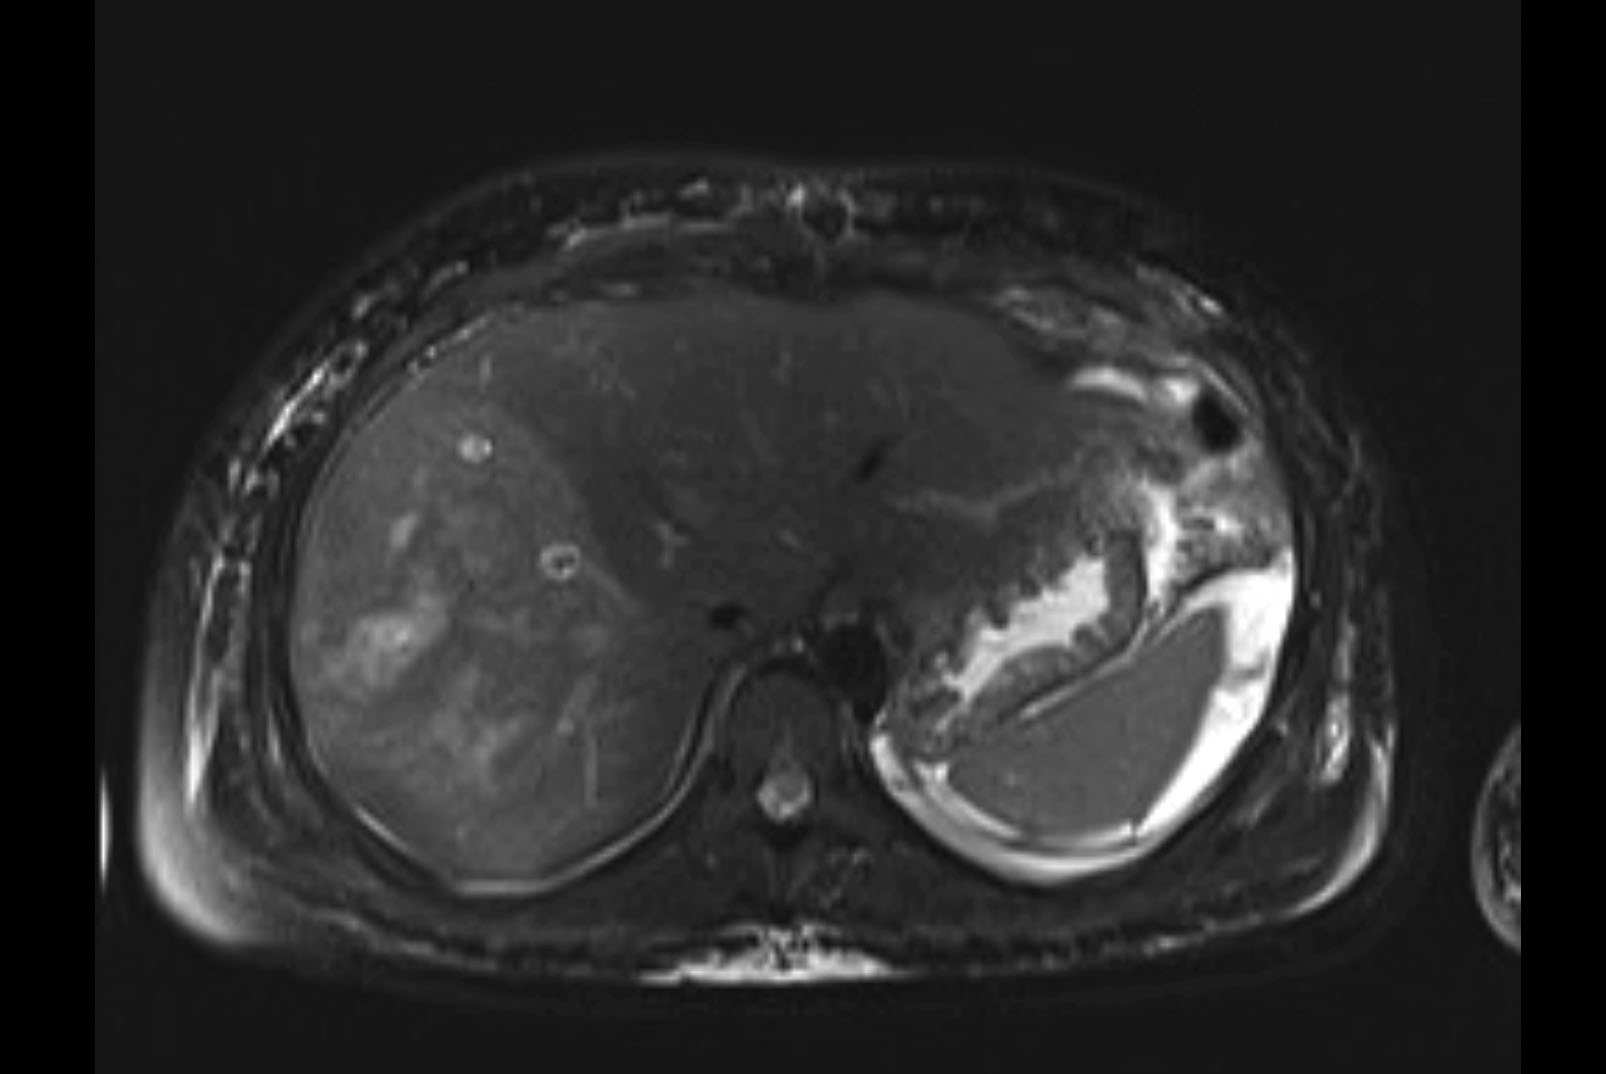

MRI T1

MRI T2

Imaging analysis

Based on initial findings, which issue(s) would you be most concerned about?